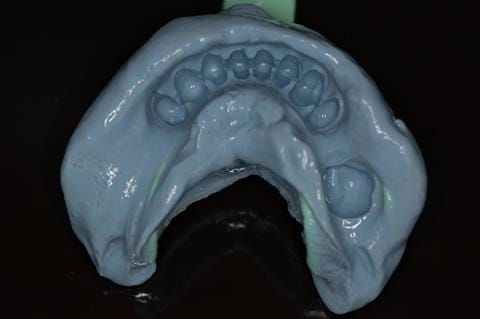

- Cobalt chromium reinforced gasket denture - using a Molloplast B "O" ring to retain and stabilise the denture. This was my professional preference as this was the least invasive and simplest solution to this dental problem. Should the UR7 require removal in the future - an artificial tooth could be added - resulting in a complete denture. The patient would have adapted to the denture fully by this stage and have good neuromuscular control of the prosthesis.

Following consultation and second discussion appointment the patient chose to have option 2 namely, a window denture - maxillary cobalt chromium based partial denture. The clinical situation and treatment process is shown in detail below with photographs. The patient was successfully rehabilitated with this and her quality of life considerably improved. The clinical work was provided by Finlay and the technical work by Rowan.